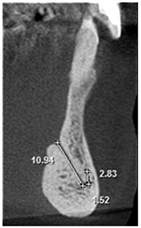

The following measurements were performed: longest width of the genial canal (W) or (D); longest length of the genial canal in relation to the alveolar bone crest (L) or (L1); (D1) or (L2), which was performed between the uppermost portion of the genial plexus and the alveolar bone crest (for dentate patients the reference was the buccal bone crest); shortest distance from the genial plexus to the buccal cortical bone (D2) or (L3), which was performed between the most vestibular portion of the genial plexus and the buccal cortical bone; (D3) or (L4), which was performed between the lowest portion of the genial plexus and the cortical part of the mandible base (Figures 1(B)-(D)).

Figure 1. Tomographic images, diameters and distances of the canal and plexus. (A) Parasagittal tomographic image; (B) Canal diameter; (C) Distance from the genial plexus to the cortical bone; (D) Initial parasagittal tomographic image, central incisor tooth. Source: Own Authorship. Caption: Parasagittal tomographic image measuring the length (A) canal diameter (B) and distances as follows: (L1) of the genial canal; (L2) distance from the genial plexus to the alveolar bone crest, (L3) distance from the genial plexus to the buccal cortical bone and the base of the mandible (L4) (C), initial parasagittal tomographic image (D). Figure 1 (A) Parasagittal section of the CBCT used to perform measurements. (B) Longest width of the genial canal (W). (C) longest length of the genial canal (L). (D) Shortest distance from the genial plexus to the alveolar bone crest (D1); shortest distance from the genial plexus to the buccal cortical bone (D2); shortest distance from the genial canal relative to the base of the mandible (D3).